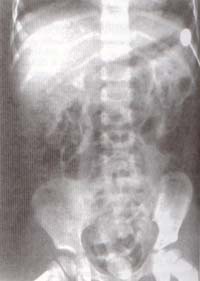

Cistografía miccional: Reflujo vesico-ureteral G3 del sistema superior derecho (Figura 1).

Figura 1

Urografía excretora: Doble sistema colector derecho, levemente dilatado el superior con cortico-medular conservada y buena función polar superior derecha. Riñón izquierdo normal. Defecto de llenamiento en piso vesical (Figura 2). Placa de evacuación post-urografía y cistografía (Figura 3).

Figura 2 Figura 3